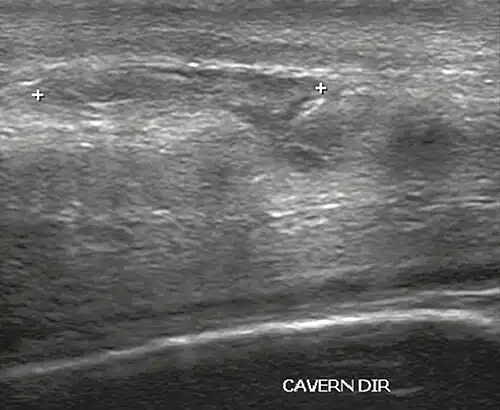

Ultrasound examination is able to depict the tunica albuginea tear in the majority of cases (as a hypoechoic discontinuity in the normally echogenic tunica). In a study on 25 patients, Zare Mehrjardi et al. concluded that ultrasound is unable to find the tear just when it is located at the penile base. In their study magnetic resonance imaging (MRI) accurately diagnosed all of the tears (as a discontinuity in the normally low signal tunica on both T1- and T2-weighted sequences). They concluded that ultrasound should be considered as the initial imaging method, and MRI can be helpful in cases that ultrasound does not depict any tear but clinical suspicions for fracture are still high. In the same study, authors investigated accuracy of ultrasound and MRI for determining the tear location (mapping of fracture) in order to perform a tailored surgical repair. MRI was more accurate than ultrasound for this purpose, but ultrasound mapping was well correlated with surgical results in cases where the tear was clearly visualized on ultrasound exam.[10] The advantage of ultrasound in the diagnosis of penile fracture is unrivaled when its noninvasive, cost-effective, and nonionising nature are considered.[11]

In the ultrasound examination, a lesion of the tunica albuginea presents as an interruption in (loss of continuity of) the echoic line representing it (Figure 4). Small, moderate, or broad hematomas demonstrate the extent of that discontinuity. Intracavernous hematomas, sometimes without the presence of a tunica albuginea fracture, can be observed when there is a lesion of the smooth muscle of the trabeculae surrounding the sinusoid spaces or the subtunical venular plexus.[2]